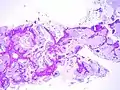

Mucinous BAC